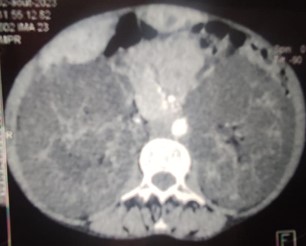

Faced with the observation of hepatomegaly and abdominal distention on clinical examination, an abdominal CT scan was requested. Thus, we were able to objectify polyrenal hepatocellular cystic disease (Figures 1 and 2).

Figure 1: Axial CT scan image of the abdomen revealing a polycystic liver.

Figure 2: Axial CT scan image of the abdomen showing two large polycystic kidneys.